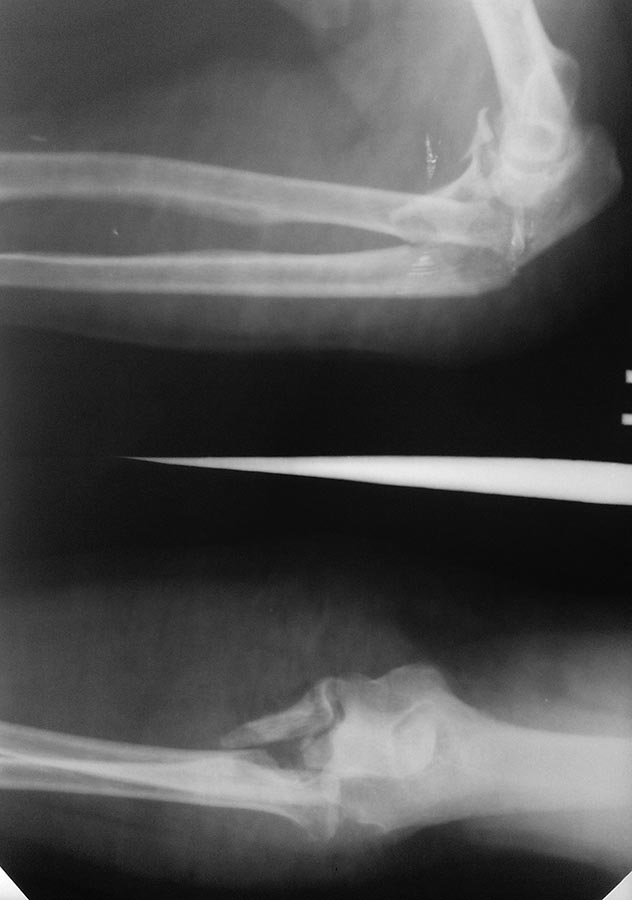

Пациентка 66 лет. Перелом закрытый. Как синтезировать лучевую кость?

Повреждение Монтеджа - перелом локтевой с вывихом головки луча. Синтезировать локтевую премоделированной LCP, головку луча вправить и зафиксировать спицей.

Здесь сложный переломо-вывих в локтевом суставе. Вывих лучевой и перелом можно трактовать как чрез-локтевой-разгибательный вариант перелома Монтеджа. Проксимальный отдел локтевого проходит через расщепленный короноид. Вывих луча приводит к укорочению предплечья и на снимке наслоение костей, поэтому всегда надо иметь снимки после репозиции. Возможно, имеются снимки, где показан перелом лучевой кости, но на представленных снимках, кроме подозрения на перелом головки луча, ничего не видно.

Следующим этапом исследования было бы КТ, но при отсутствии достаточными бывают обычные снимки.

Сперва репозицию локтевого отростка в проксимальном отделе проводится лагированием сбоку, и после чего укладыается пластина. Подойдет любая пластина для фиксации локтевого отростка, а перелом короноида фиксируется через пластину шурупом. Вывих устранится, головка луча встанет на место, и нет резона фиксировать, но при наличии краевого перелома головки она фиксируется тонкими шурупами 1.5-2 мм.